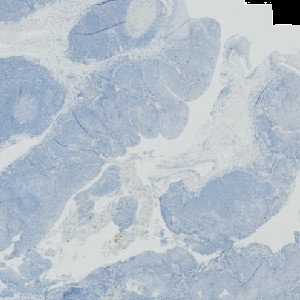

Figure 1

CK5 stained slide.